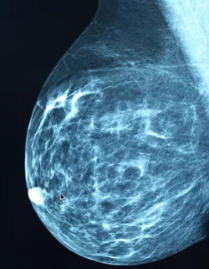

(1) 초음파 검사와 세침흡인검사

- 초음파 검사를 통해 종양의 크기와 위치를 확인합니다.

- 필요 시 세침흡인검사로 종양의 악성 여부를 판단합니다.